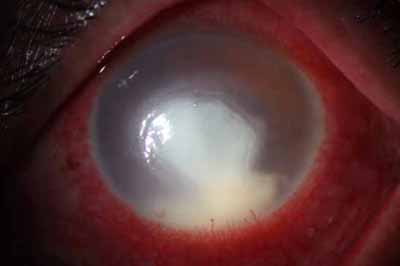

Aspecto Clínico

• Superficie corneal irregular y grisacea

• Opacidades granulares en parche

• Formación de lineas epiteliales elevadas de aspecto granular, que pueden dar imágen de seudodendritas

• Opacidades superficiales satélites

• Ulceración epitelial variante

• Formación de anillo inmunológico

• Dolor intenso (no siempre presente)

Superficie corneal irregular y grisácea

En su evolución se observará aumento del edema, aparición de un anillo inmunológico (Wessely), agrandamiento y coalescencia de los infiltrados que progresan hacia la formación de un absceso, queratolisis superficial, adelgazamiento y perforación corneal.

Anillo inmunológico de Wessely